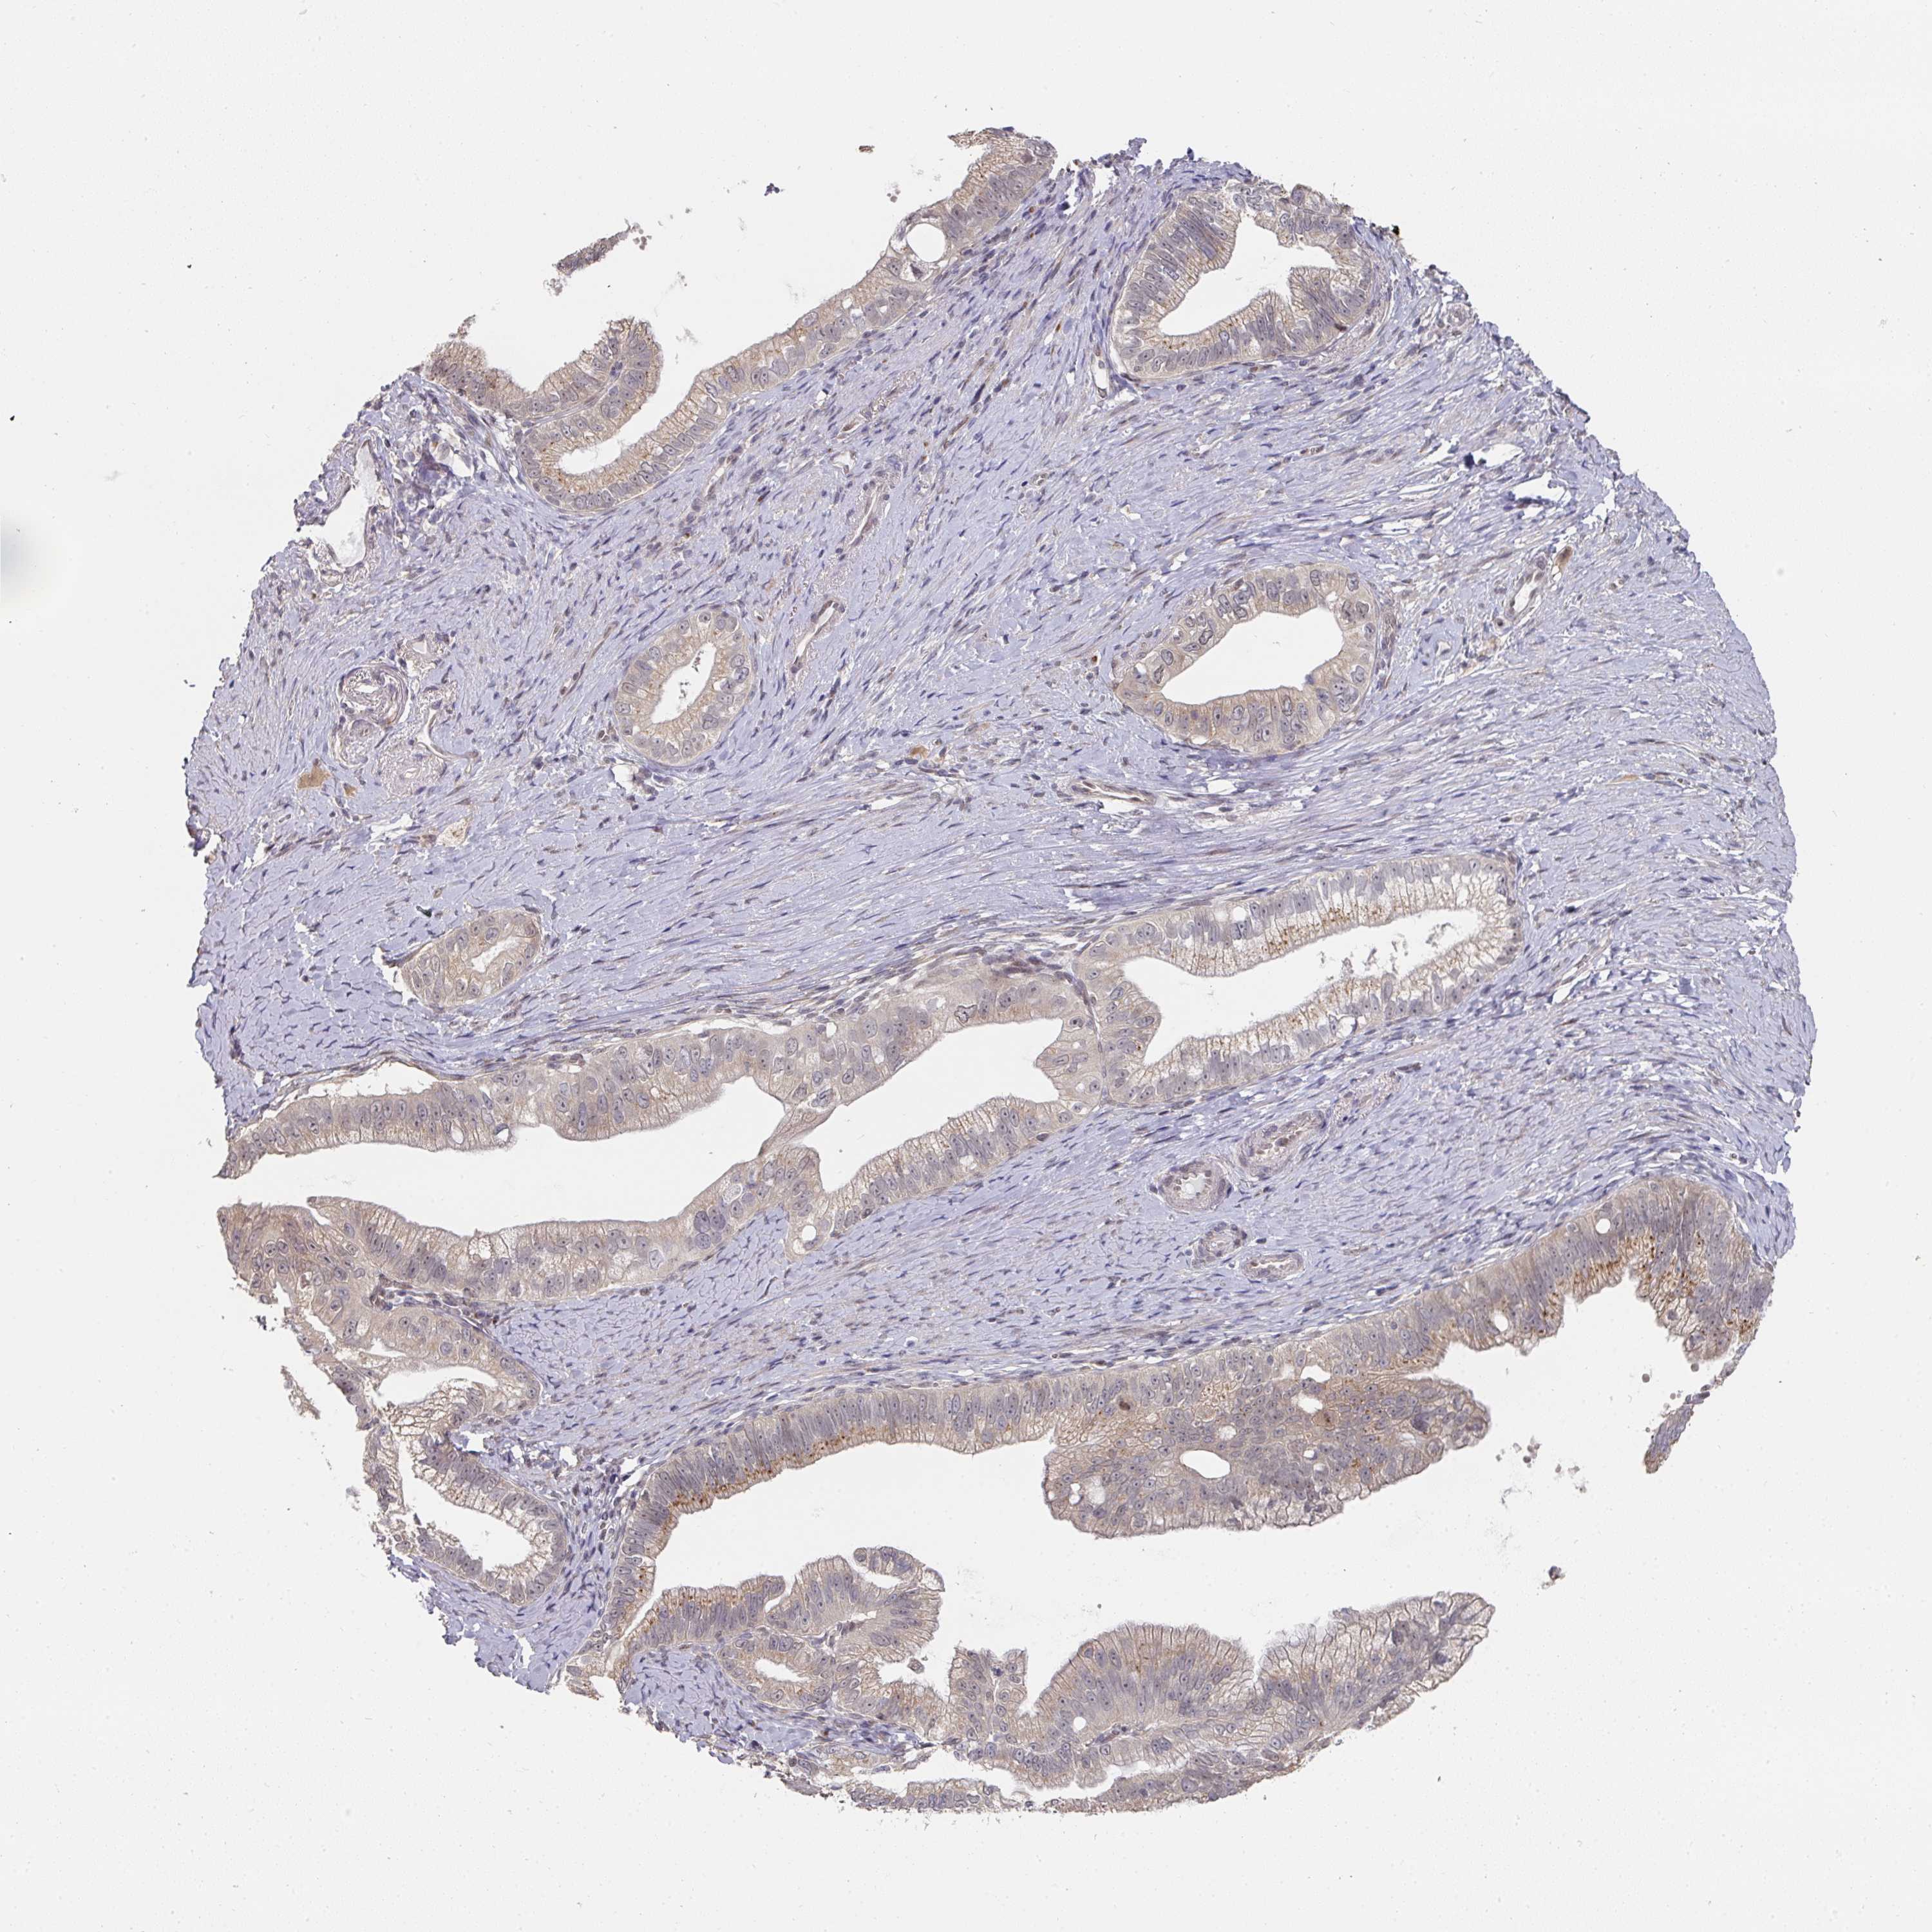

PANCREATIC CANCER - Protein expressioni

A mouse-over function shows sample information and annotation data. Click on an image to view it in a full screen mode. Samples can be filtered based on level of antibody staining by selecting one or several of the following categories: high, medium, low and not detected. The assay and annotation is described here.

Note that samples used for immunohistochemistry by the Human Protein Atlas do not correspond to samples in the TCGA dataset.

Antibody stainingi

Antibody staining in the annotated cell types in the current human tissue is reported as not detected, low, medium, or high, based on conventional immunohistochemistry profiling in selected tissues. This score is based on the combination of the staining intensity and fraction of stained cells.

Each image is clickable and will lead to virtual microscopy that enables deeper exploration of all samples and also displays staining intensity scores, fraction scores and subcellular localization as well as patient and tissue information for each sample.

Antibody HPA051314

Staining

High

Medium

Low

Not detected

Intensity

Strong

Moderate

Weak

Negative

Quantity

>75%

75%-25%

<25%

None

Location

Nuclear

Cytoplasmic/membranous

Cytoplasmic/membranous,nuclear

Adenocarcinoma, NOS